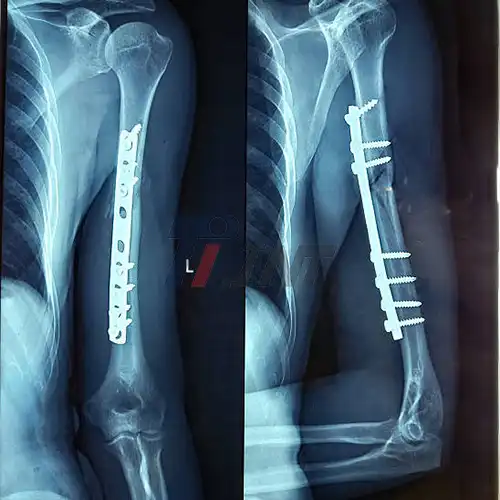

The use of a titanium plate for bone fracture is a sophisticated medical procedure that requires precision and expertise. The process begins with a thorough assessment of the fracture, including imaging studies such as X-rays, CT scans, or MRIs to determine the exact nature and location of the break. Once the fracture is fully understood, the surgeon selects the appropriate titanium plate. These plates come in various shapes and sizes, each designed for specific types of fractures and anatomical locations. For instance, a plate used for a femur fracture will differ significantly from one used for a wrist fracture.

The surgical procedure, known as open reduction and internal fixation (ORIF), involves making an incision to access the fractured bone. The surgeon then carefully aligns the broken bone fragments, a process called reduction. This step is crucial as proper alignment is essential for optimal healing and restoration of function. With the bone fragments aligned, the titanium plate is positioned across the fracture site. The plate is secured to the bone using titanium screws, which are drilled into pre-determined holes in the plate. These screws, also made of biocompatible titanium, work in tandem with the plate to provide stable fixation of the fracture.